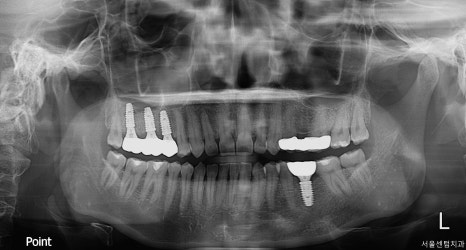

임플란트 식립 및 골이식

상악동 거상술을 시행한 부분을 보면

오른쪽 위 첫번째와 두번째 큰 어금니 부위는

크레스탈 접근법(crestal approach)을

이용한 상악동 거상술을 진행했습니다.

위쪽 3개 임플란트 식립 완료

임플란트 식립하는 구멍을 통해 상악동막을

거상을 하는 방식인데요.

아래쪽 임플란트

매우 정밀하게 진행을 해야합니다.

측방 접근법에 비해서는 침습자체가 적고

회복이 빠르다는 장점이 있습니다.

각 임플란트 부위마다 적절한 골이식재를

사용했고 인접 치아의 장축과 평행하게

정확한 각도로 식립하는 것이 중요하거든요.

초기에 고정력도 다행히도 양호하게

진행이 된 편이라 힐링 어버트먼트를

장착한 채로 골유착을 기다리기로

환자분에게 말씀드렸습니다.